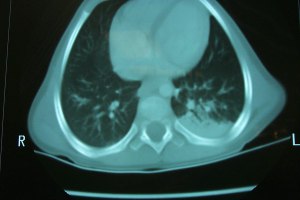

Anesthesia for CT – Spontaneous ventilation without positive pressure during general anesthesia often results in atelectasis (posterior left lung).